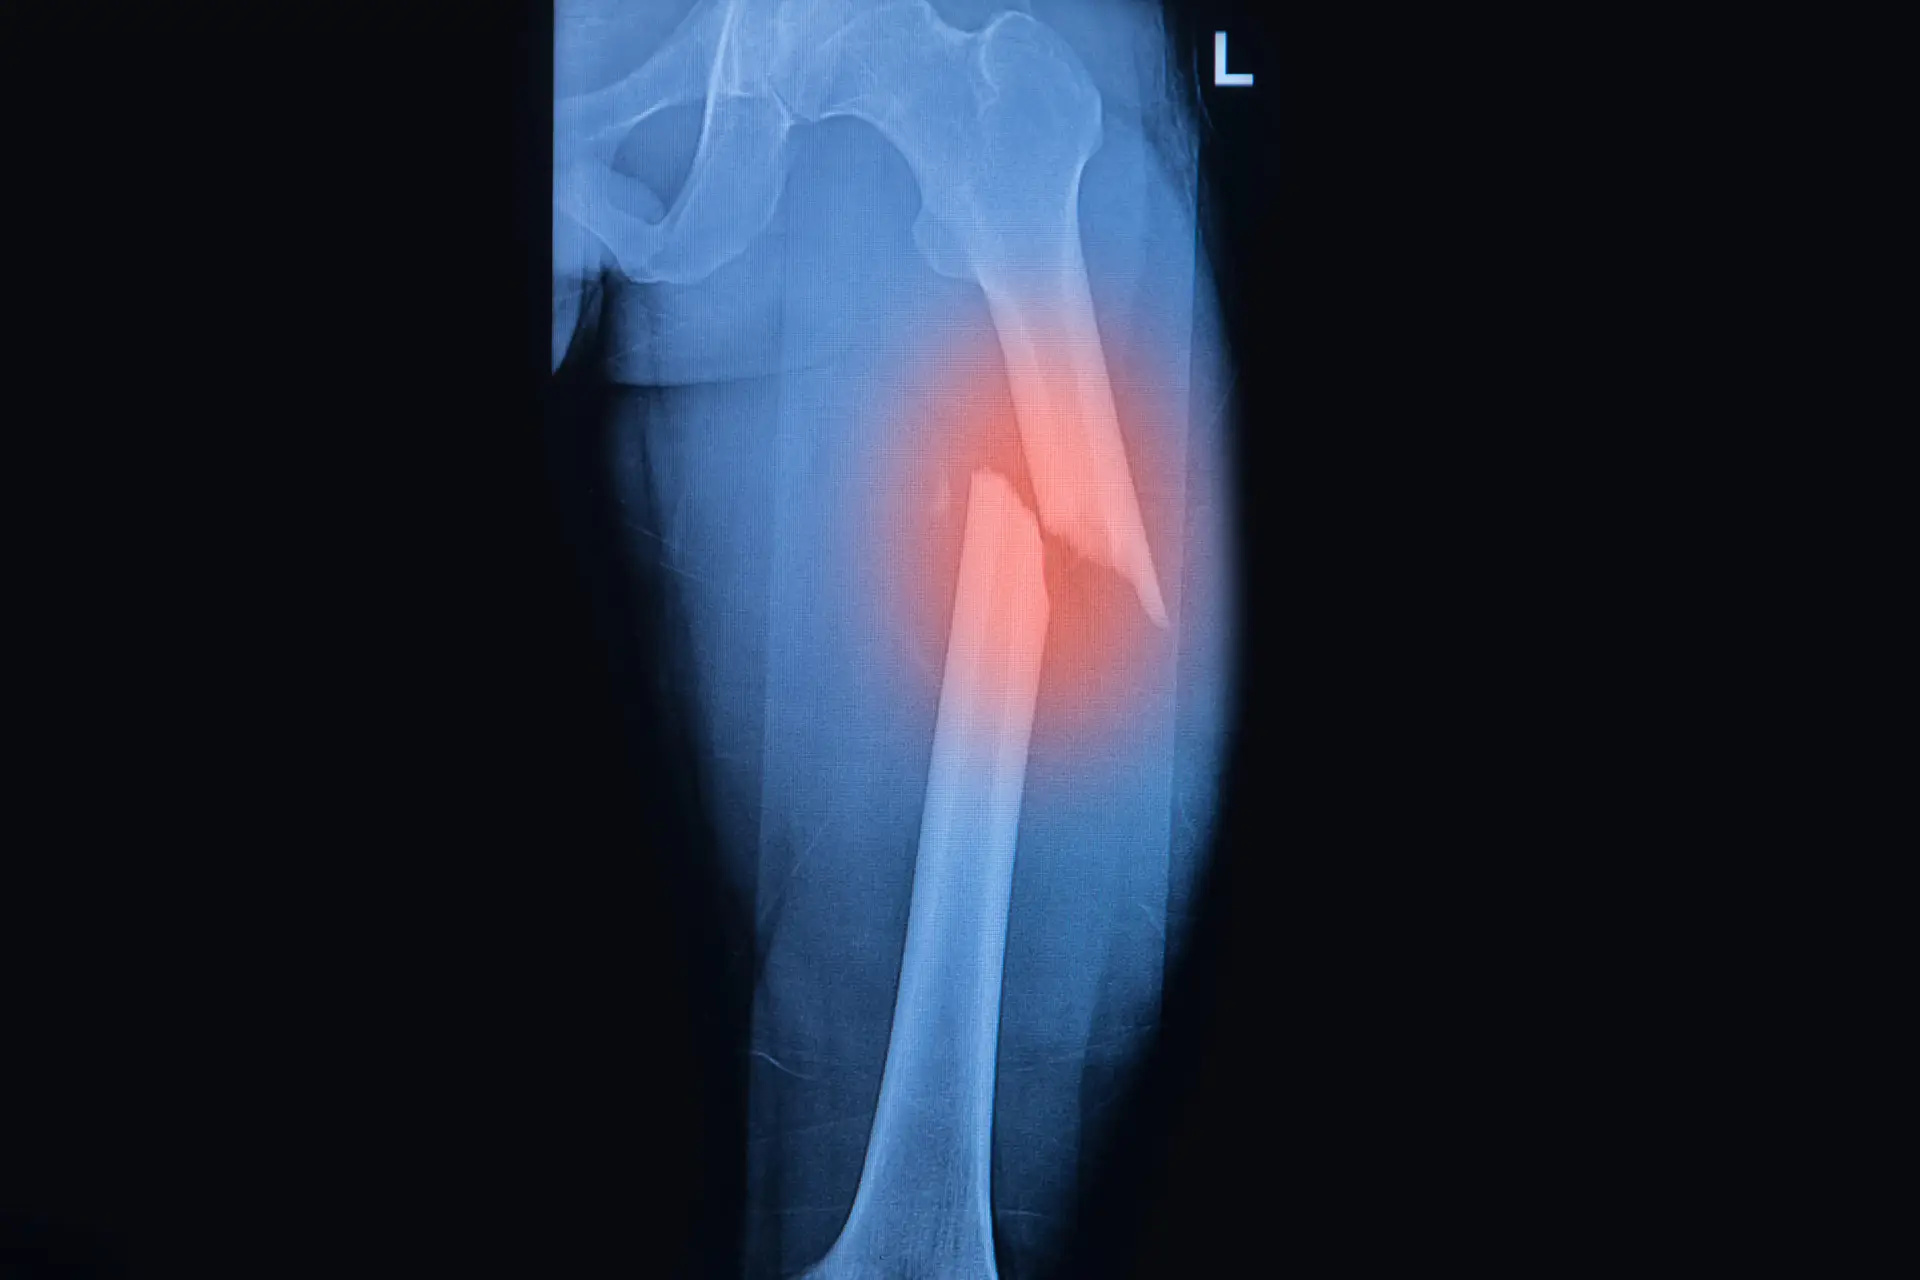

a highlighted mri photo of a broken femur highlighted with red

Your femur connects your hip to your knee. When this bone breaks, your body suffers damage to the surrounding muscles, tendons, and ligaments. You need immediate medical intervention to realign the bones and preserve the damaged tissue around your fracture.

Your doctor uses X-rays and CT scans to see exactly how your femur broke. Most femur fractures require surgery within 24 to 48 hours of your injury. This timing matters for your recovery and reduces your risk of complications.